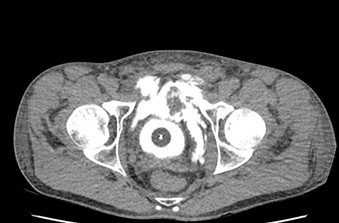

Imaging

- CECT Abdomen with Cystogram

Types of Bladder Injuries

- Extra peritoneal Bladder Injury

- Intraperitoneal Bladder Injury

Extra peritoneal Bladder Injury

Intraperitoneal Bladder Injury

Management

- Conservative management for uncomplicated extraperitonel bladder injuries

- All penetrating or intraperitoneal injuries should be managed by immediate operative repair